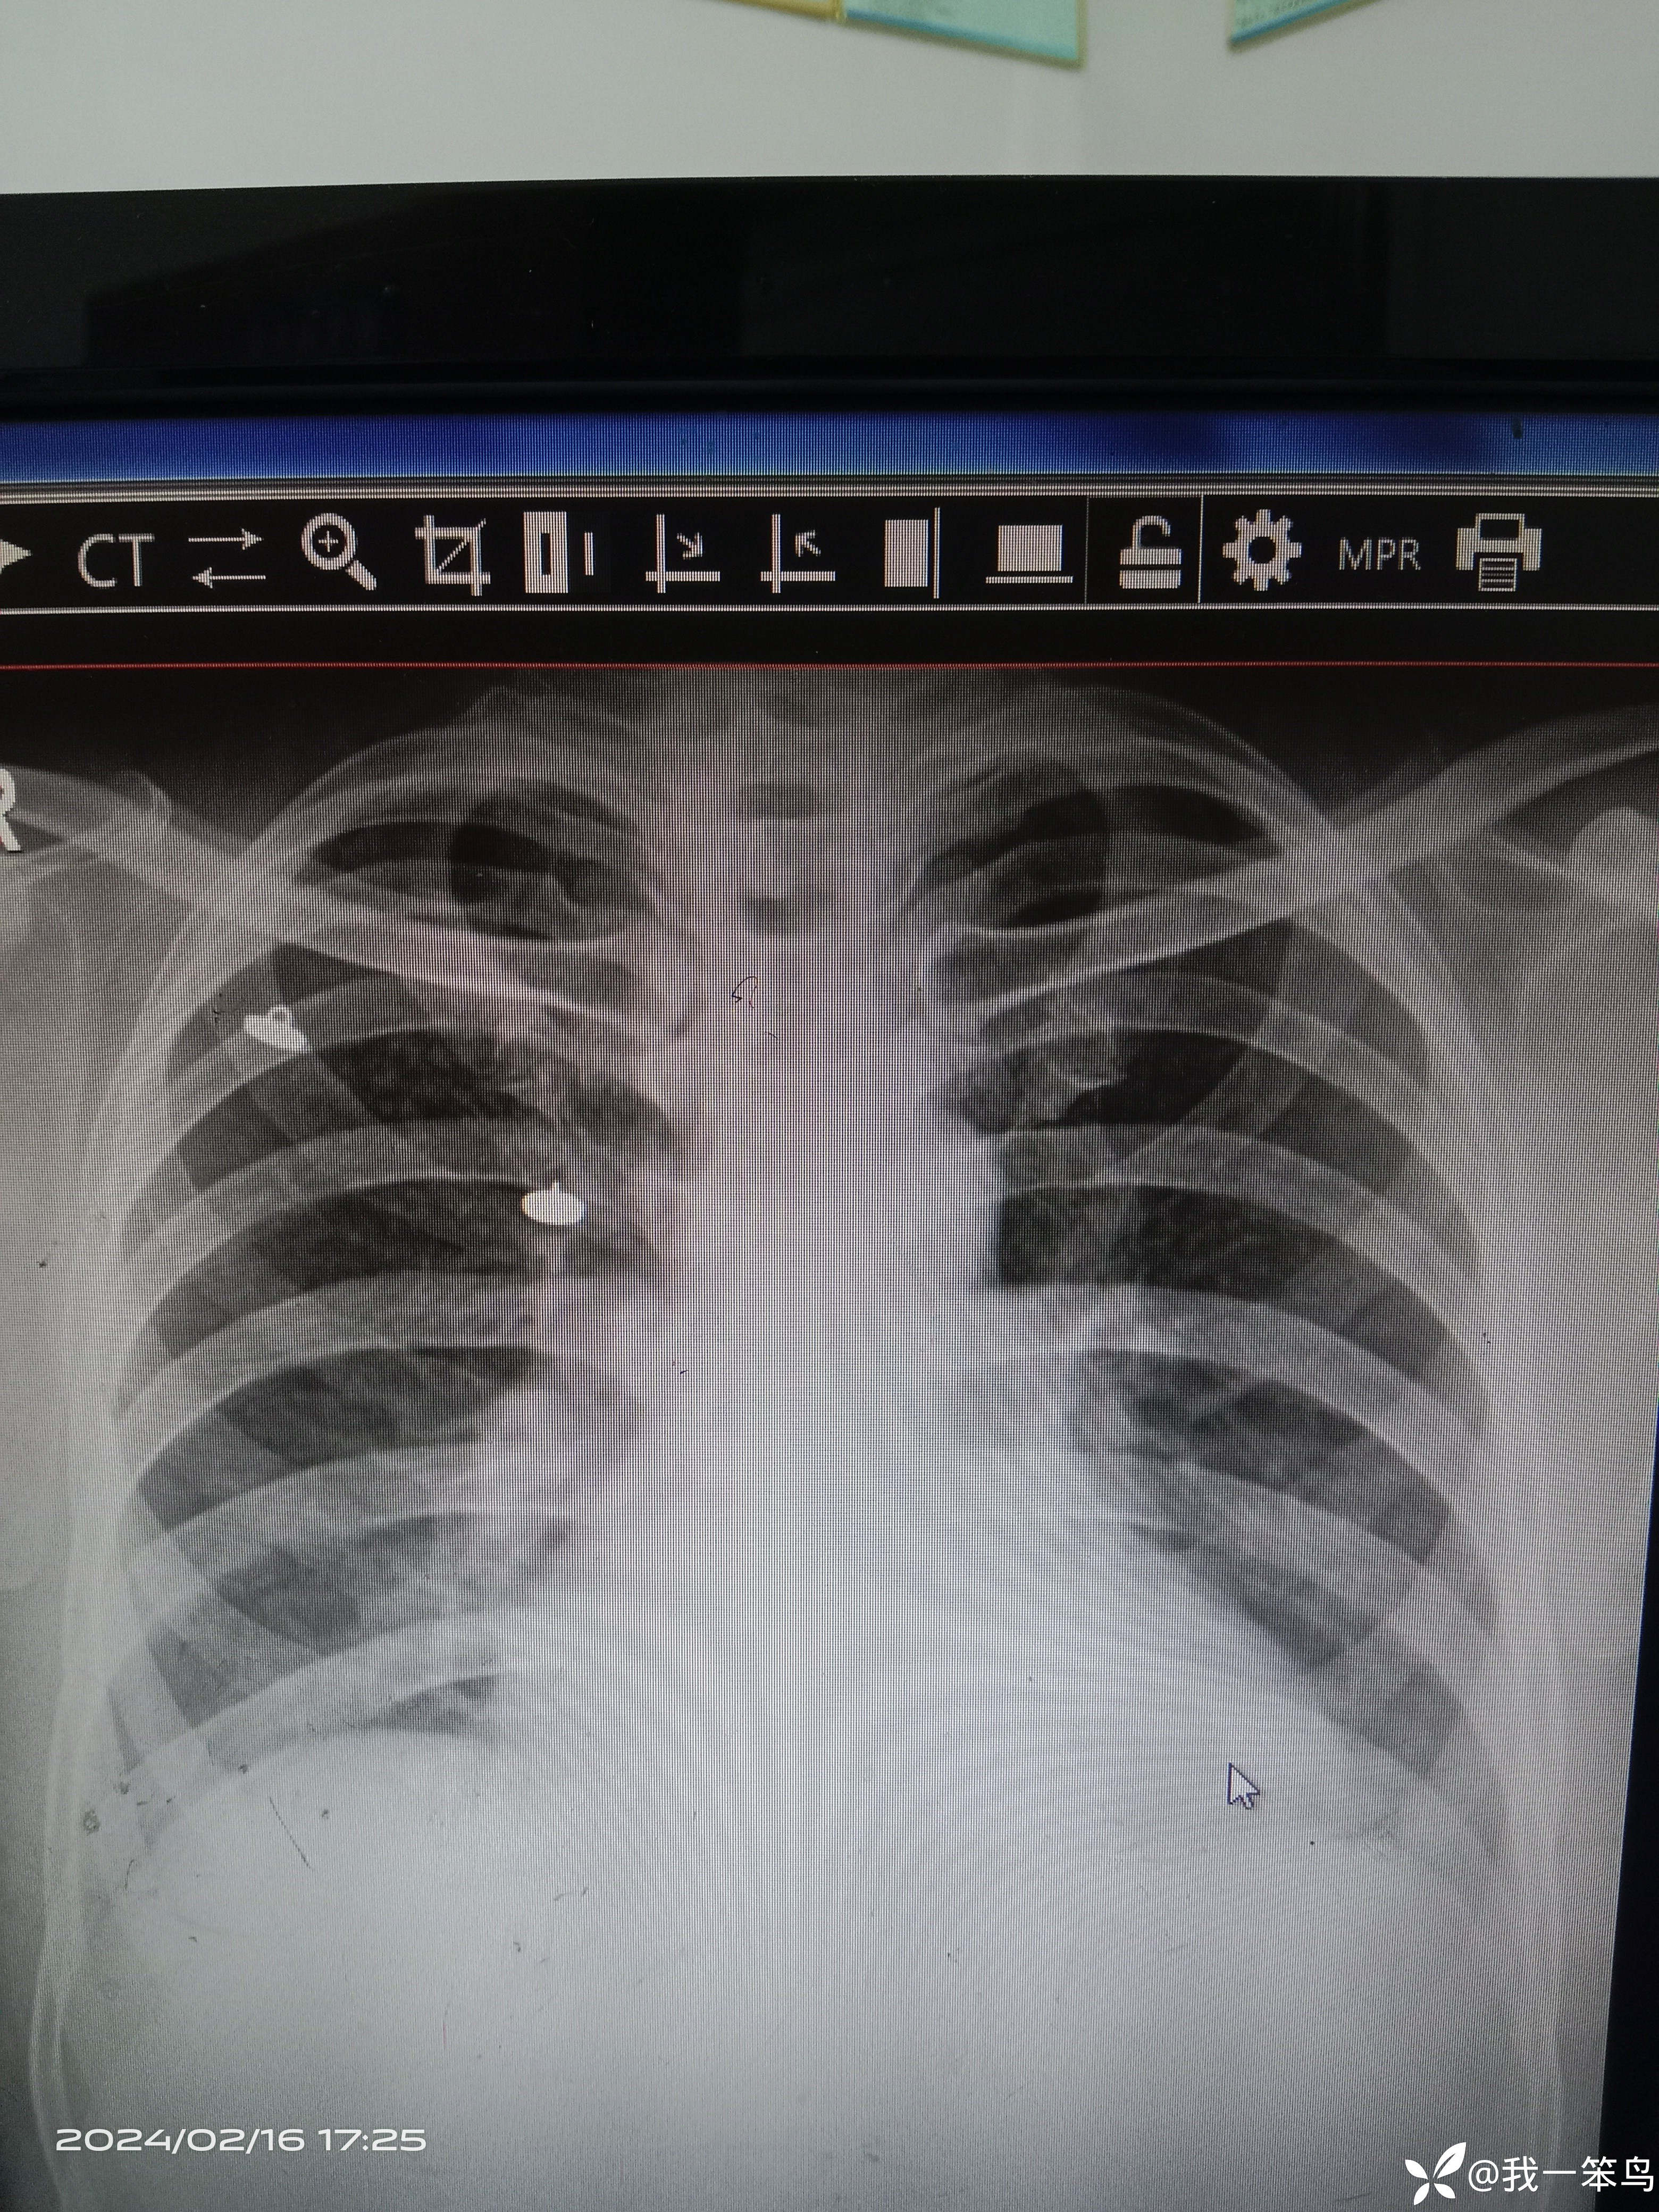

主诉:反复咳嗽、咳痰间断血痰11年,加重伴胸闷,气促、咯血10天

现病史: 患者既往从事煤矿井下工作多年,于11年前开始出现咳嗽.咳痰,剧烈时痰中血丝症状,并逐渐加重伴活动后胸闷、胸痛、气促,2010被矽肺鉴定小组确诊为“Ⅰ期矽肺”,曾多次在省职业病防治院住院治疗,予以肺灌洗,抗肺纤维化、润肺化痰、提高免疫力及对症支持治疗后,好转出院。此次发病于10多天前,患者不慎受凉后再次出现咳嗽咳痰,阵发性,咳白色粘稠痰,量多,间断性咳血,伴活动后气促、胸闷、胸痛,无畏寒、发热,无恶心、呕吐症状,自行在家口服药物治疗(具体用药不详),疗效欠佳,遂来我院就诊,以“Ⅰ期矽肺并肺部感染”收入住院治疗。此次发病以来,患者食欲精神可,大小便正常。

拟诊:1.Ⅰ期矽肺;2.咳血查因:a继发性肺结核?b肝功能异常?C血小板减少症?d血液病?3..冠心病,心脏扩大,心绞痛型,心功能2级。